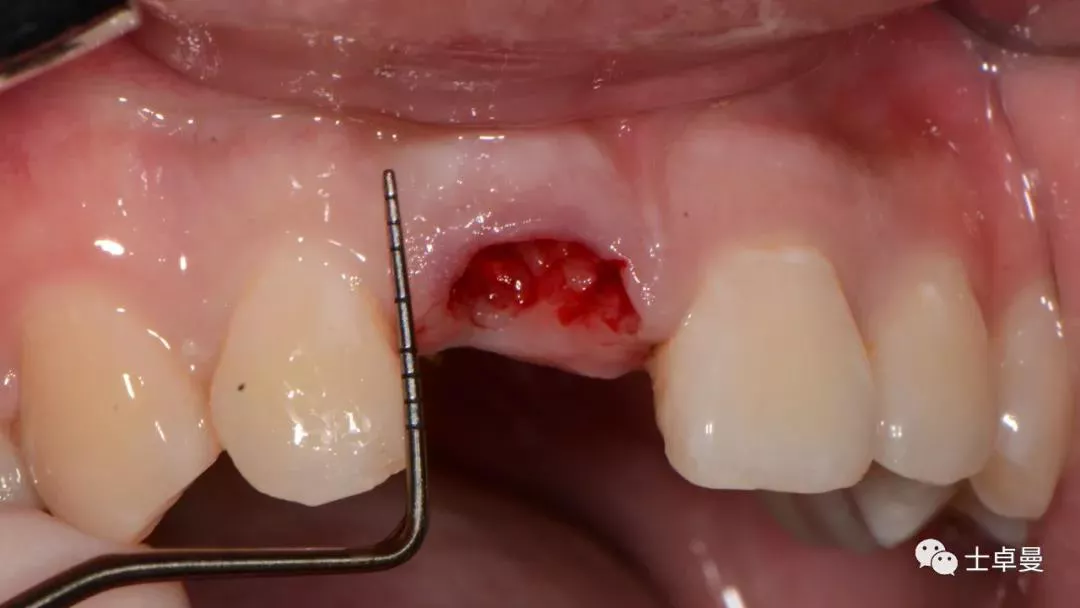

就位种植外科导板

指示杆观察备孔三维位置

种植体植入后,植体唇侧间隙内填塞骨粉0.25g,胶原骨100mg,安放愈合帽,明胶海绵暂时封闭创面

术后即刻CT示,种植体植入位置理想